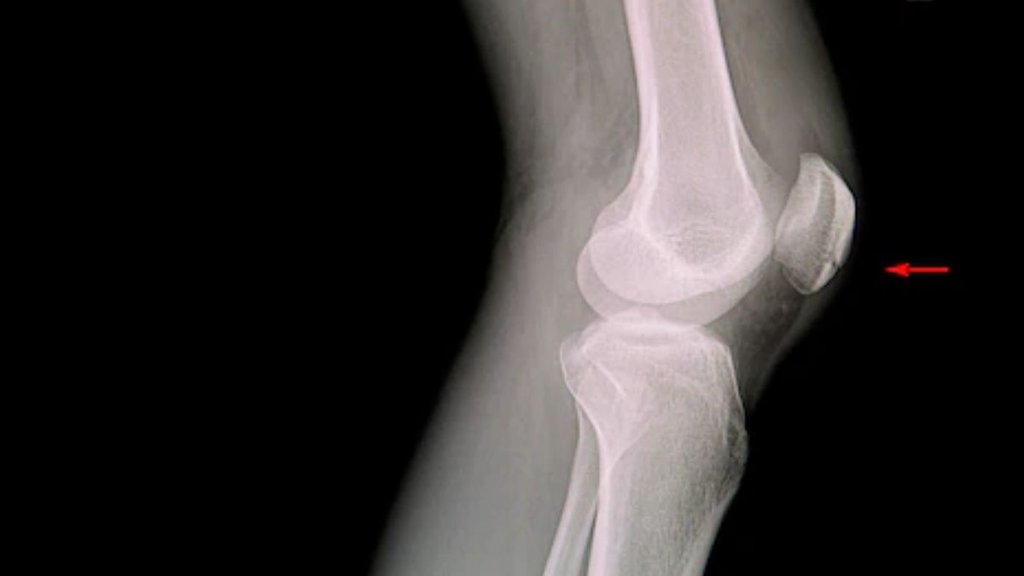

PGI रोहतक के ऑर्थोपेडिक सर्जन डॉक्टर हरि सिंह मीणा ने जनसत्ता डॉट कॉम से बातचीत में बताया कि अचानक दुर्घटना, खेलते समय चोट लगना, अचानक से झटका लगना, कूदते समय गलत तरीके से उतरना घुटने के लिगामेंट्स को नुकसान पहुंचा सकता है। घुटने के जोड़ में चार प्रमुख लिगामेंट हैं जिनमें ACL – एंटीरियर क्रूसिएट लिगामेंट, PCL – पोस्टीरियर क्रूसिएट लिगामेंट, MCL – मेडियल कोलेटरल लिगामेंट, LCL – लेटरल कोलेटरल लिगामेंट शामिल हैं। इसके अलावा दो मिनिस्कस भी होते हैं जो घुटने की कार्टिलेज का एक हिस्सा है। घुटने के जोड़ को स्थिर रखने के साथ ही हड्डियों को घिसने से बचाने में मदद करता है। आमतौर पर अचानक मूवमेंट के कारण मिनिस्कस फट या टूट जाते हैं, जब घुटने को अचानक उसकी क्षमता से अधिक मोड़ा जाता है।

डॉक्टर मीणा ने बताया कि घुटने का महत्वपूर्ण हिस्सा एंटीरियर क्रूसिएट लिगामेंट (ACL) है। यह लिगामेंट खेल चोटों में सबसे अधिक टूटता है। फटे लिगामेंट को फिर से जोड़ने और एक नया लिगामेंट बनाने की प्रक्रिया को ACL रीकॉन्ट्रक्शन कहते है। लिगामेंट आपके शरीर में मजबूत ऊतकों का समूह होता है जो हड्डियों को आपस में जोड़ता है। घुटने की आर्थ्रोस्कोपिक प्रक्रियाओं में एसीएल सर्जरी सबसे प्रभावी है।

एसीएल सर्जरी घुटने को लोकेट रखने में मदद करती है। फुटबॉल, बास्केटबॉल और स्कीइंग में जब घुटना ज्यादा खिंच जाता है तो लिगामेंट में फटने की स्थिति पैदा हो जाती है। ऐसे में घुटना सूज जाता है और उसमें दर्द होने लगता है। घुटना डिसलोकेट हो जाता है और चलने में कठिनाई होती है। इसके अलावा दो मिनिस्कस भी होते हैं जो घुटने की कार्टिलेज का एक हिस्सा है। घुटने के जोड़ को एक साथ बनाए रखने के साथ ही हड्डियों को घिसने से बचाने में मदद करता है। आमतौर पर अचानक मूवमेंट के कारण मिनिस्कस फट या टूट जाते हैं, जब घुटने को अचानक उसकी क्षमता से अधिक मोड़ा जाता है।

डॉक्टर मीणा के मुताबिक आर्थ्रोस्कोपिक पद्धति से अब लिगामेंट्स का सफलतापूर्वक इलाज संभव है। कोई भी लिगामेंट जो फटा हुआ है, बिना चीरा लगाए आर्थोस्कोप की मदद से उसकी मरम्मत या रिपेयर किया जाता है। अर्थरोस्कोप रिपेयर के लिए हेम्सट्रिंग मसल्स से ग्राफ्ट ले कर नया लिगामेंट का निर्माण करते हैं। चोट के कारण लिगामेंट के फटे हुए हिस्से को हटा दिया जाता है। नतीजतन, घुटने की अस्थिरता समाप्त हो जाती है और दर्द से राहत मिलती है।